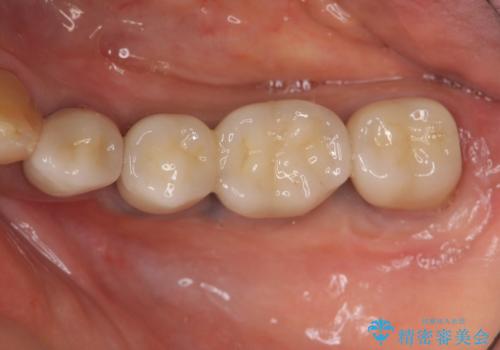

- 100万円(ストローマンインプラント×2・仮歯×4・チタンカスタムアバットメント×2・ジルコニアクラウン×4)費用は治療当時の料金となります

ブリッジ治療は支台となる歯が弱いと、今回のように周囲の骨が吸収したり歯が割れてしまったりといったトラブルがおきます。咬合力に対抗するため、今回はインプラントを用いて機能回復を行いました。